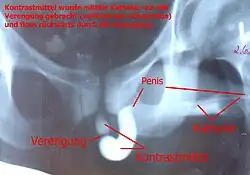

Retrograde urethrogram

![]() Urethrogram showing an urethra stricture in a man. | |

A retrograde urethrography[1] is a routine radiologic procedure (most typically in males) used to image the integrity of the urethra. Hence a retrograde urethrogram is essential for diagnosis of urethral injury, or urethral stricture.[2][3]